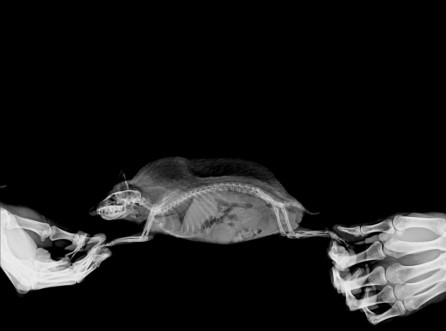

슈가글라이드- 중성화, 감돈포경(or Penile pr...